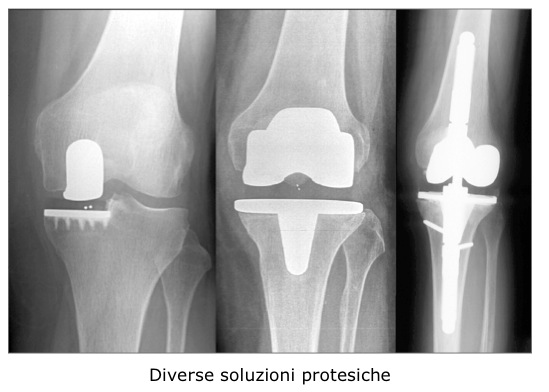

Il chirurgo, sulla base dell’esame clinico e radiografico, saprà stabilire la necessità dell’intervento in funzione della patologia, dell’età e delle aspettative del paziente. I dati raccolti orientano nella scelta del tipo di protesi più indicata al caso specifico.

Tra le soluzioni proposte esistono protesi totali, dove tutta l’articolazione viene sostituita, o protesi monocompartimentali dove invece si sostituisce soltanto “metà” articolazione. Quanto ai materiali di cui sono composte le protesi, distinguiamo per semplicità protesi non cementate, ovvero ad ancoraggio diretto osso-protesi, e protesi cementate, legate all’osso mediante cemento acrilico.

Per l’ancoraggio delle protesi non cementate, il materiale che attualmente riunisce in sé le migliori caratteristiche è la lega di titanio.

Le protesi cementate sono invece costituite di preferenza da leghe metalliche a maggiore rigidità (es. ProtasulÒ-S30 FeCrNiMnMo) per esigenze di accoppiamento con il cemento.

La Comunità Europea, attraverso il sistema di norme I.S.O., vigila sulla qualità e biocompatibilità dei materiali impiegati. La scelta del tipo di protesi varia in funzione dell’età, della patologia, della qualità dell’osso ricevente ed è comunque sempre affidata all’esperienza del chirurgo.